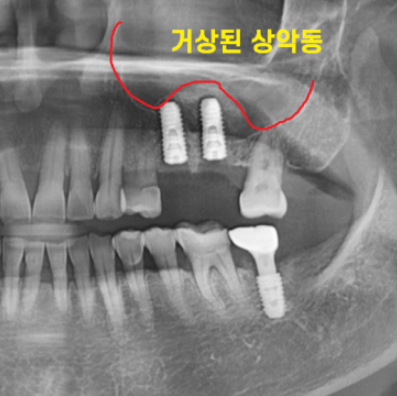

임플란트를 위해 ct 촬영을 시행했습니다.

치아 뿌리 끝과 상악동 구조물이 너무 가깝네요.

지난 시간에 임플란트를 심기 위해서는

최소 8~10mm 길이가 필요하다고 말씀드렸죠~?

부족한 길이만큼 상악동을 들어 올려

뼈 이식 후 임플란트를 해야겠네요.

진단 결과 남아있는 뼈의 두께도 얇고

치아 뼈 폭도 좁아서 Lateral 방법으로 진행하기로 상담 드렸습니다.

수술 후 사진입니다.

상악동을 올리면서 뼈이식을 진행하여

돔 형태로 잘 만들어진 것이 확인됩니다.

이제 기다렸다가 완성하는 일만 남았습니다.